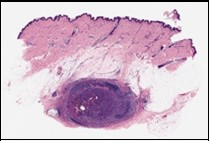

Ultrastructural evaluation is devoid of pertinent cellular features. However, modified endothelial cells, smooth muscle cells, striated muscle cells, histiocyte- like cells, fibroblast- like cells and miniature, interdigitating cellular processes conjoined by desmosome- like junctions are discerned5, 6. Figure 1, Figure 2, Figure 3, Figure 4, Figure 5, Figure 6, Figure 7, Figure 8.

Figure 1.Angiomatoid fibrous histiocytoma demonstrating a multinodular pattern with circumscribing lymphoid and plasma cell infiltrate and a superimposed stratified squamous epithelium 9